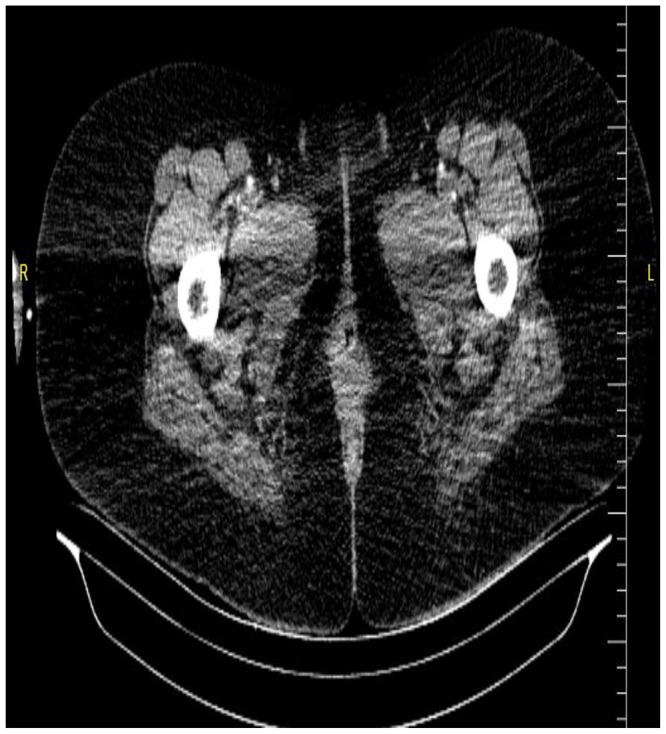

产后女性急性肢体缺血是一种罕见且严重的血管急症,如果不及时诊断和治疗,可能导致严重的并发症。31岁女性,采用取石位阴道分娩后30天,出现双侧下肢麻痹和感觉异常,分娩过程中无外伤、跌倒或辅助器械使用史。患者体重65公斤,身高162厘米,而婴儿的出生体重为2.8公斤。最初怀疑是神经系统疾病,后来通过影像学排除,包括胸腰椎MRI和CT血管造影,显示双侧动脉闭塞。尽管及时进行了血栓栓塞切除术,但由于进行性缺血,患者接受了双侧膝下截肢。本病例强调了产后急性肢体缺血的诊断挑战,强调了早期影像学和及时的多学科干预在预防严重后果中的关键作用。提高临床警惕性和及时调查对于改善预后和减少肢体丧失的风险至关重要。

Acute limb ischemia in postpartum women is a rare and severe vascular emergency that can lead to significant complications if not promptly diagnosed and managed. A 31-year-old woman, 30 days postpartum following uncomplicated vaginal delivery in the lithotomy position, presented with bilateral lower limb paralysis and paresthesia There was no history of trauma, falls, or use of assistive instruments during delivery. The patient weighed 65 kg and was 162 cm tall, while the infant had a birth weight of 2.8 kg. Initial suspicion of a neurological condition was later ruled out through imaging, including thoracolumbar MRI and CT angiography, which revealed bilateral arterial occlusions. Despite timely thromboembolectomy, the patient underwent bilateral below-knee amputation due to progressive ischemia. This case highlights the diagnostic challenges of acute limb ischemia in postpartum patients, stressing the crucial role of early imaging and prompt multidisciplinary intervention in preventing severe outcomes. Increased clinical vigilance and timely investigations are vital for improving prognosis and reducing the risk of limb loss.